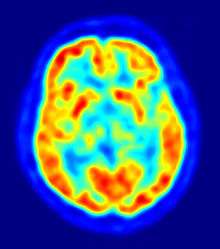

Magnetic Resonance Imaging scan of a head PET taken with an ECAT Exact HR+ PET Scanner

PET taken with an ECAT Exact HR+ PET Scanner